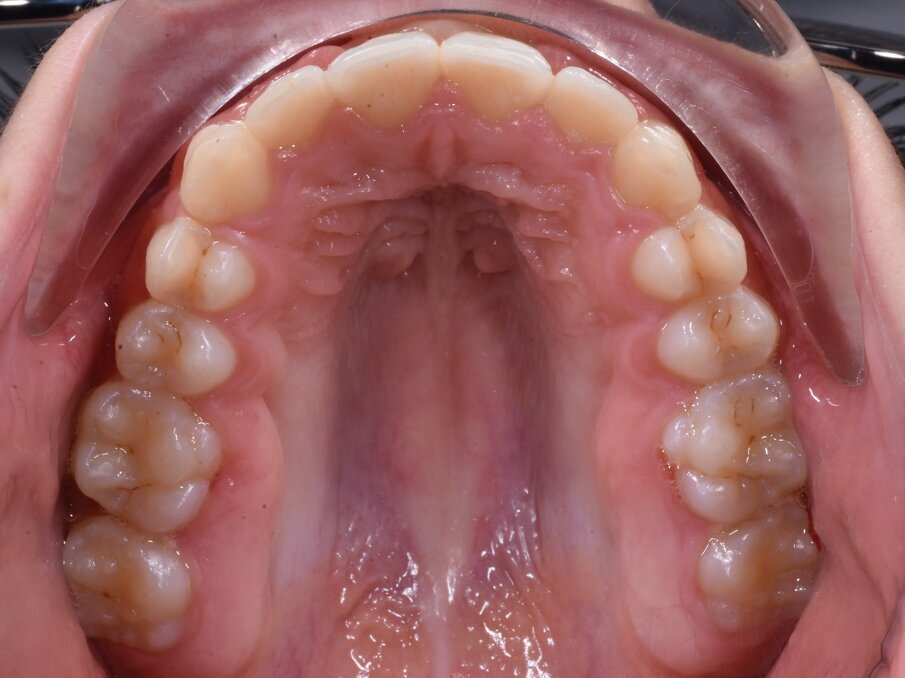

_Materiale e metodi Una paziente di sesso femminile di 11 anni, presenta all’esame clinico: dentizione permanente, palato di forma ogivale, discrepanza trasversale, affollamento e contrazione dell’arcata superiore, tipping vestibolare dei primi molari superiori, marcato affollamento dentale inferiore, tipping linguale degli elementi dentali postero-inferiori, proinclinazione vestibolare degli incisivi inferiori (Fig. 1). La paziente, inoltre, riferisce il menarca sei mesi prima dell’inizio della terapia. Per prima cosa è stato realizzato un setup digitale del risultato finale nell’arcata inferiore correggendo l’affollamento mediante espansione dei settori posteriori e minimizzando la proinclinazione degli incisivi. Utilizzando questo setup digitale come arcata guida, è risultata una discrepanza trasversale tra arcata inferiore e arcata superiore di circa 6 mm (Fig. 2).Richiesto l’esame CBCT, è stata valutata anche la morfologia della sutura palatina ed è risultata di tipo C secondo la classificazione di Angelieri et al11 (Fig. 3).

Fig. 1_Situazione intraorale a inizio terapia.